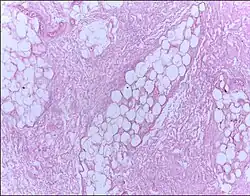

| Micrograph of breast tissue showing fat necrosis. H&E stain | |